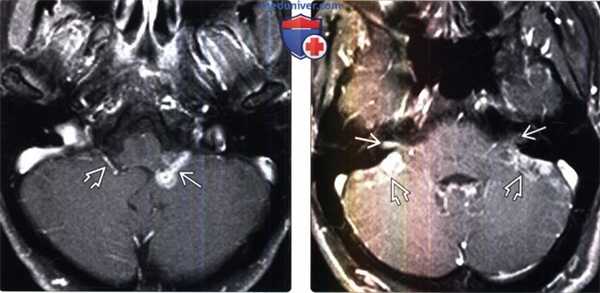

(Слева) МРТ, постконтрастное Т1-ВИ, режим подавления сигнала от жира, аксиальный срез: у пациента с верифицированными отдаленными метастазами рака прямой кишки определяется контрастирование метастаза, в сосудистом сплетении нижней части цистерны ММУ и отверстия Люшки. Также визуализируется нормальное сосудистое сплетение справа.

(Справа) МРТ, постконтрастное Т1 -ВИ, режим подавления сигнала от жира, аксиальный срез: с двух сторон в областях ММУ-ВСП определяются «падающие» метастазы супратенториальной мультиформной глиобластомы. Наряду с двусторонними контрастируемыми метастазами во ВСП, на поверхности мозжечка выявляются множественные лептоменингиальные метастазы.